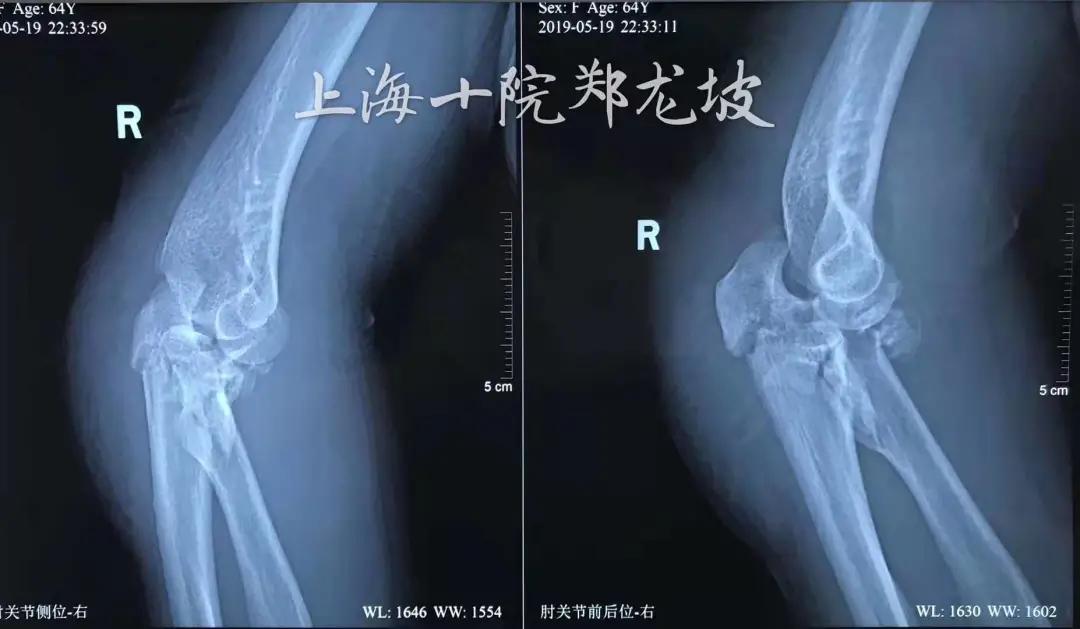

患者张阿姨64岁,不久前外出时,遇车祸导致右肘关节疼痛、活动受限,被送往上海十院救治,影像学检查提示肘关节恐怖三联征,合并尺骨鹰嘴骨折。

创伤骨科郑龙坡主任与团队充分讨论

指出患者为“向后孟氏骨折脱位”,

既尺骨鹰嘴骨折后脱位型,

合并有冠状突和桡骨小头的粉碎骨折,

比肘关节恐怖三联征治疗起来更有难度。